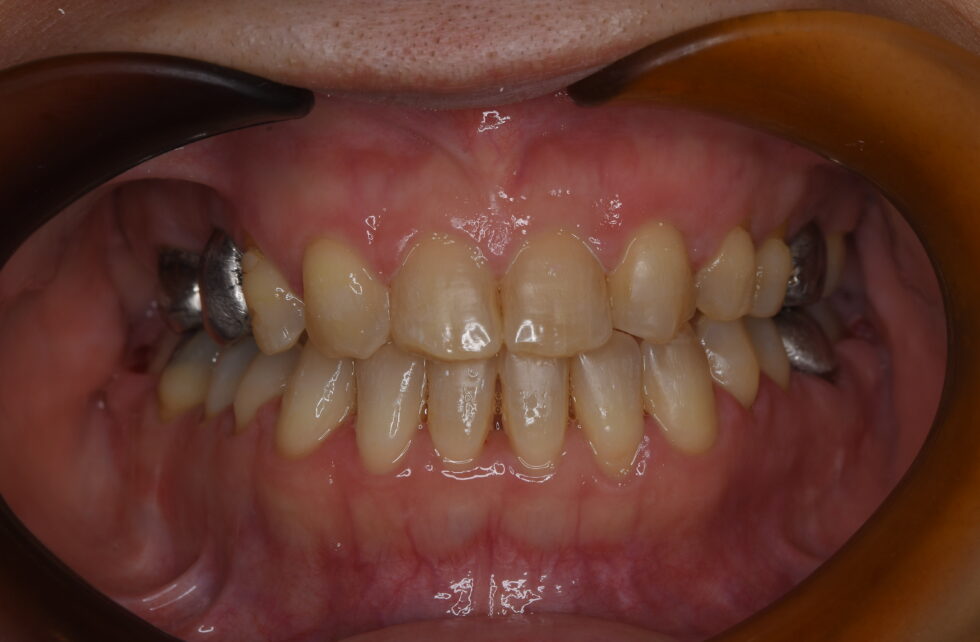

初診時年齢52歳の女性 前歯部の反対咬合を主訴にご来院いただいた。

全ての前歯部が反対咬合となって、上顎左右側側切歯は先天欠損、上顎右側第一大臼歯は欠損してブリッジによる補綴処置が行われていた。セファログラム他の分析を行い骨格性反対咬合と診断した。矯正治療単独では被蓋の改善が十分行えないと評価し、顎離断術を併用した外科矯正を計画した。先天欠損である上顎側切歯部の空隙を閉鎖するように術前矯正を行い顎離断術を行った。手術後、術後矯正を行い保定へ移行した。前歯部の被蓋は改善し、上顎前歯の空隙の閉鎖が行われた。動的治療期間:術前、術後合わせ3年8カ月間